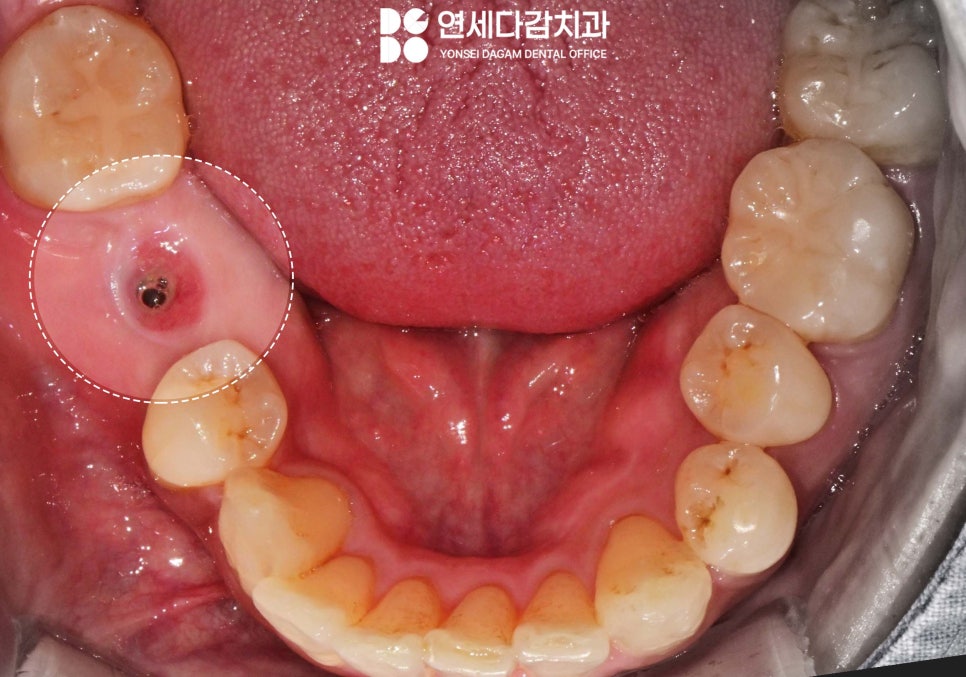

만약 고정체(fixture)와 어버트먼트를

연결하는 보철 나사(screw)가

부러지게 된다면,

임플란트 상부 구조물이

흔들리고 빠지게 됩니다.

거여역 치과 에서 보여드린 것처럼

보철이 부러지는 일이 있을 땐

교체가 필요합니다.

거여역 치과 에서 보여드린 증례는

다행히도 두 번째 방법을 이용하여

얇은 잇몸 치료 전용 팁을

장착하여 진동을 줬을 때

잘 빠진 모습입니다.

내부 모습도 나사 일부가

잘 빠져나온 것을 확인한 뒤